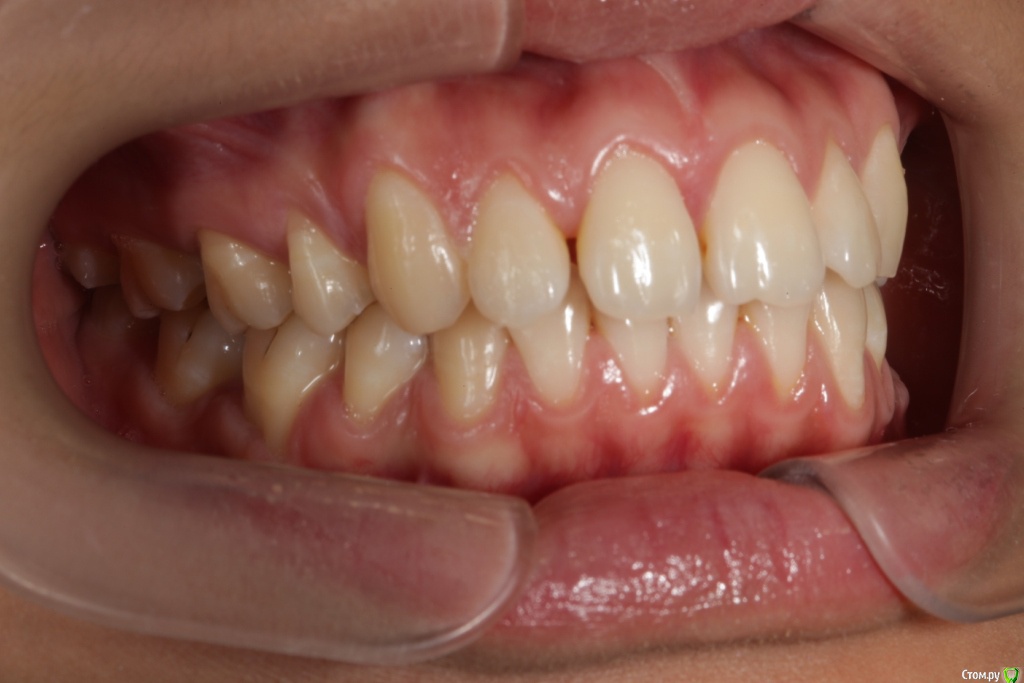

Головные боли, артроз ВНЧС, дистальный глубокий прикус, удалены 4ки на вч и 5 на нч

Сейчас мне 25 лет. С детства был дистальный глубокий прикус, зубы на верхней челюсти выпирали вперед, на нижней челюсти присутствовала скученность, из-за чего была удалена "мешающая" 5ка. Вероятно, этот зуб стоило сохранить.

В 2007-2008 гг. проходила ортодонтическое лечение с удалением 4ок на верхней челюсти. Резцовые зубы были перемещены назад, эстетически результат был удовлетворительным. Однако, проблема неправильного прикуса решена не была.

То, что эти боли могут быть следствием проблем с ВНЧС, узнала в последнюю очередь. МРТ показало, что у меня артроз суставов - 3 степени слева, полная вентрально-латерация дислокация суставного диска без репозиции; 1 степени справа, с репозицией, гипермобильность правого сустава. Асимметрии лица нет, однако рот открывается по S-образной траектории (почти не заметно), при широком открывании рта очень редко слышен щелчок, хрустов нет, слегка выпирает правый сустав. Заключение по МРТ с подробным описанием в приложении.

P.S: необходимо ли закрывать рецессии до начала лечения? или лучше сделать это после окончания лечения?